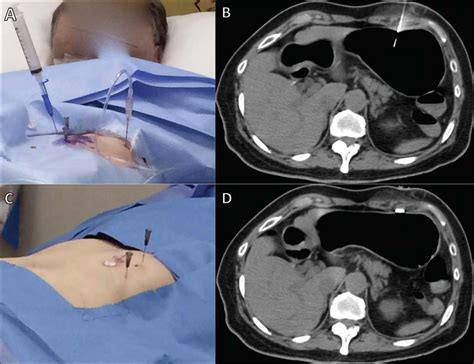

The Percutaneous Endoscopic Gastrostomy is a minimally invasive procedure, usually performed by a gastroenterologist. It involves the use of an endoscope—a thin, flexible tube with a camera—to visualize the inside of the stomach while the physician creates a small opening in the abdominal wall. Through this incision, a feeding tube is inserted directly into the stomach, allowing for a long-term route for enteral nutrition.

Before undergoing a Percutaneous Endoscopic Gastrostomy, patients are typically required to stop eating or drinking for several hours to ensure the stomach is empty. The medical team will review current medications, particularly blood thinners, as these may need to be paused to minimize the risk of bleeding during the procedure. Anesthesia, usually in the form of conscious sedation, is administered to keep the patient comfortable throughout the process.

The actual placement is relatively quick, usually taking less than 30 minutes. Once the tube is secured, the surrounding area is cleaned and covered with a sterile dressing. Patients are monitored closely in the recovery area before being allowed to resume gentle movement or transition to home-based care.